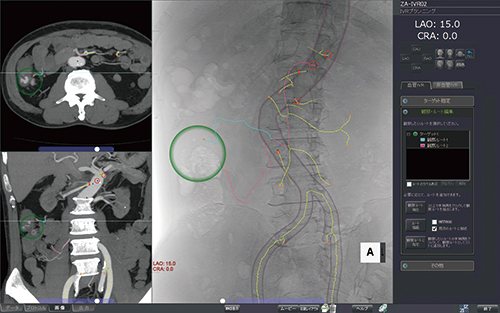

IVRプランニング

CT画像を基に透視に似た画像を作成,血管を自動抽出して,救急などでの塞栓術を支援する。一刻を争いスピードと精度が要求される救急現場での要求に応え,臨床医の手技をサポートする。